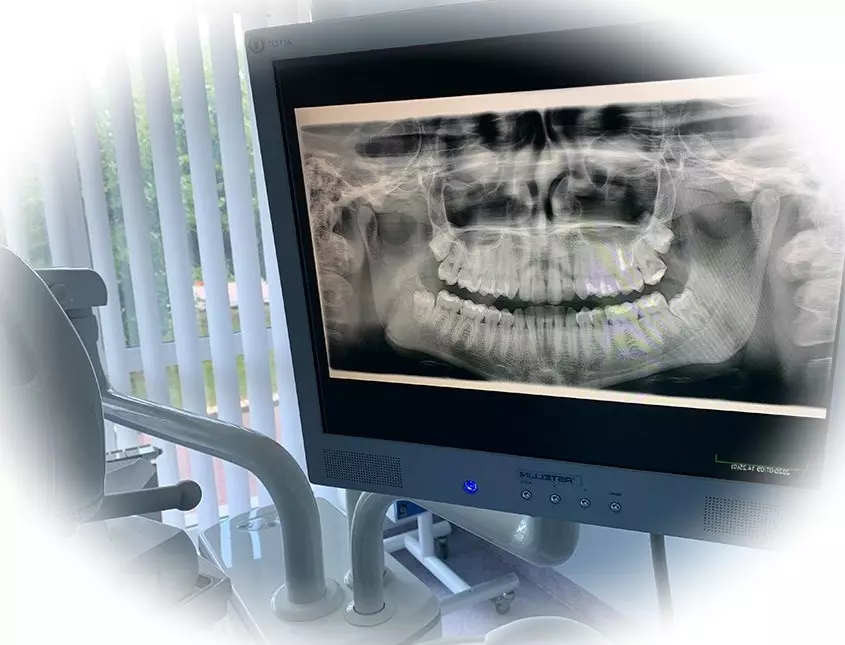

- Получение результата. Обработка кадров выполняется специальным ПО, которое формирует объемное 3D изображение. Именно по этим данным специалист проводит интерпретацию визуальных данных. Результат предоставляется пациенту в электронном формате.

Важно! Полученная информация позволяет с высокой точностью диагностировать заболевание, составить план лечения и провести оценку позитивных результатов всех видов стоматологической помощи. Результат КТ будет полезен не только стоматологу, ортодонту или хирургу-имплантологу. Например, снимок гайморовых пазух поможет в диагностике заболеваний ЛОР-органов.